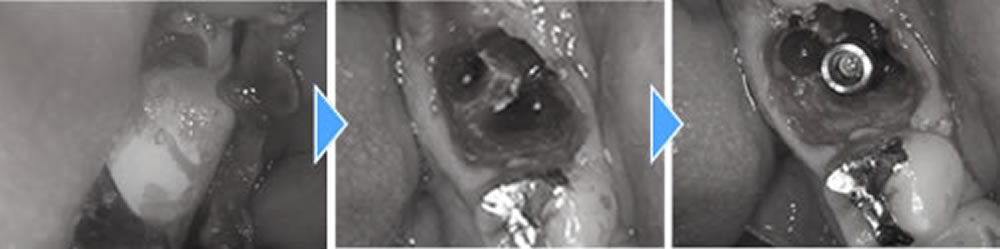

1つ前の歯も抜歯後に中を綺麗にし、インプラント埋入、骨造成までを1度のオペで行っていきました。こちらはインプラントの蓋が外に出るような形にして縫合しました。

このオペが終わってから4ヶ月置き、しっかりと骨とインプラント体が結合している事を確認した後、上部の歯を作成していきました。